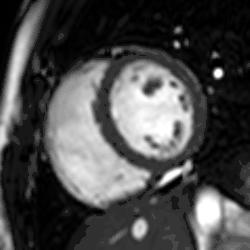

Perfusion

Adenosine is used as a vasodilator, via the A2A receptor, to increase the difference in perfusion between myocardial territories supplied by normal and stenosed coronary arteries. A continuous intravenous infusion is administered for a few minutes until there are hemodynamic signs of vasodilatation, then a bolus of contrast medium is administered while acquiring saturation recovery images of the heart with a high temporal resolution readout. A positive result is evident from an inducible myocardial perfusion defect. Cost and availability mean that its use is often confined to patients with intermediate pre-test probability,[24] but it has been shown to reduce unnecessary angiography compared with guidelines-directed care.[25]